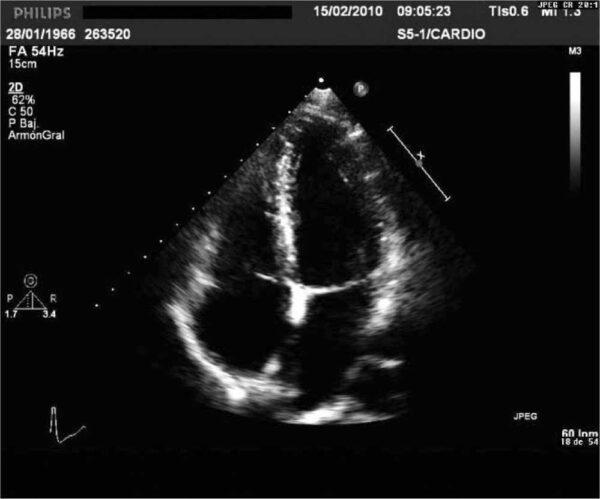

Un ecocardiograma es una prueba diagnóstica no invasiva que utiliza ondas de ultrasonido para obtener imágenes detalladas del corazón. Es una herramienta fundamental en la evaluación de la estructura y función cardíaca, ya que permite visualizar el corazón en movimiento y proporciona información sobre su tamaño, forma, capacidad de bombeo y la integridad de las válvulas cardíacas.

- Ecocardiograma transtorácico (ETT): Es el tipo más común de ecocardiograma y se realiza colocando el transductor sobre el pecho del paciente. Permite obtener imágenes detalladas del corazón desde diferentes ángulos y proporciona información sobre la anatomía y función cardíaca, incluyendo el tamaño y grosor de las paredes del corazón, la función de las cámaras cardíacas, el flujo sanguíneo a través de las válvulas y la presencia de anomalías estructurales.